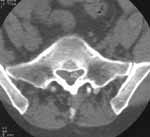

Иногда возникали диагностические сложности при диагностике фораминальных, некоторых секвестрированных грыж, которые потеряли контакт с диском и далеко сместились в спинно- мозговом канале. В 5 случаях пришлось дифференцировать секвестрированную грыжу с опухолями и эпидуральными абсцессами. Секвестры существовали длительное время, были заключены в рубцовую ткань, введение магневиста способствовало получению высокого сигнала в виде ободка вокруг секвестра, что помогло отдифференцировать его от опухоли (Рис. 1).

Рис. 1. Большая секвестрированная грыжа диска L5-S1. (а) Сагитальный скан до контрастирования.

Рис. 1. Большая секвестрированная грыжа диска L5-S1. (б) Аксиальный скан после введения магневиста.